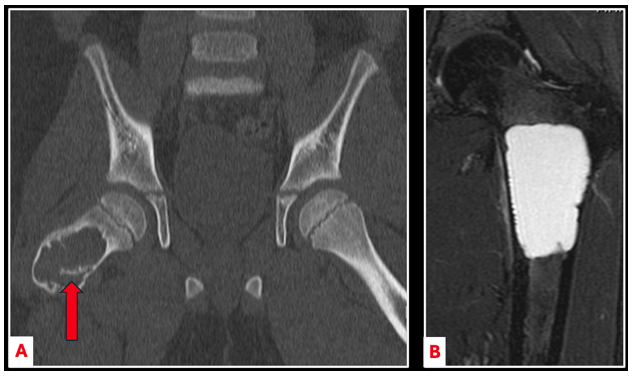

On imaging, unicameral bone cysts (UBCs) are typically seen in the center of the bone, with thinning of the surrounding bone wall (cortex) (Figure 1). UBCs can grow large and cause the bone to expand, making it thin and weak. Sometimes, small pieces of bone can break off and fall into the cyst cavity — a feature known as the “fallen leaf sign” (Figure 2A).

On MRI scans, UBCs appear as fluid-filled cavities without any solid tissue or soft tissue mass around them (Figure 2B).

Figure 2. CT-scan imaging demonstrating the “fallen leaf sign” (red arrow) where a piece of bone fractures and falls into the cyst cavity (A). MRI-imaging demonstrating a large, fluid-filled cyst within the central aspect of a femur, consistent with a UBC (B).